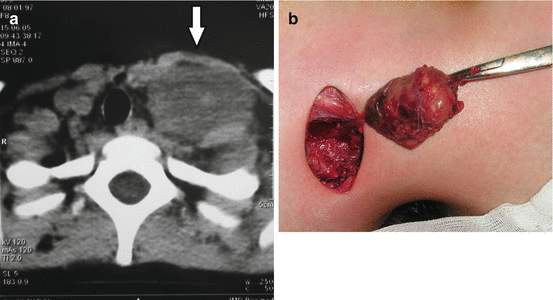

Fine needle biopsy, core needle biopsy, and incisional or excisional biopsy are used as diagnostic tools for rhabdomyosarcoma, followed by light microscopic examination, immunohistochemistry, electron microscopy, and cytogenetic analysis [5, 17–19]. Magnetic resonance imaging (MRI) and computerized tomography (CT) are used for tumor and lymph node evaluation [3, 8, 20, 21]. There are three histologic types of RMS: embryonal, alveolar, and undifferentiated (pleomorphic) [2, 3, 8, 17]. Embryonal tumors are found in 80–85% of cases and they mostly occur at birth, and alveolar occurs at adolescent period (worse prognosis) (Fig. 12.1a, b) [2, 3, 15]. RMS can be present in syndromes such as Li-Fraumeni and Beckwith-Wiedemann syndrome [3, 18]. Metastasis of RMS is primarily by hematogenous route [17, 19].

Fig. 12.1

Rhabdomyosarcoma of the head: (a) intraoperative view; (b) tumor biopsy